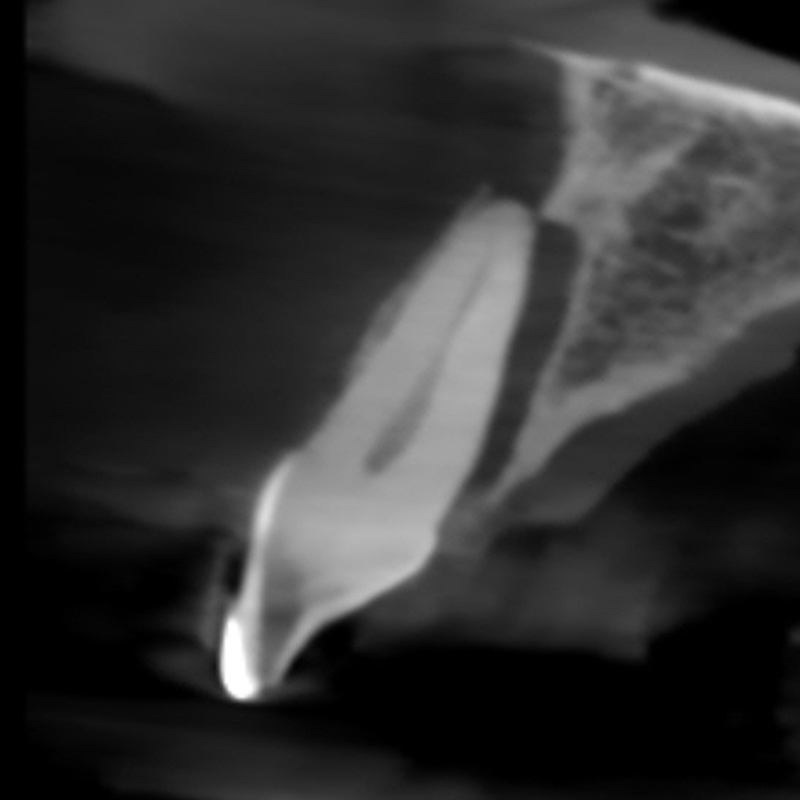

Resorption

Resorption is a condition where the tooth’s structure starts to break down, either from the inside out or from the outside in. It can be caused by trauma, inflammation, or other factors. Endodontic treatment for resorption involves removing the damaged tissue and reinforcing the tooth with materials that help prevent further damage. The aim is to save the tooth and maintain its functionality as much as possible.